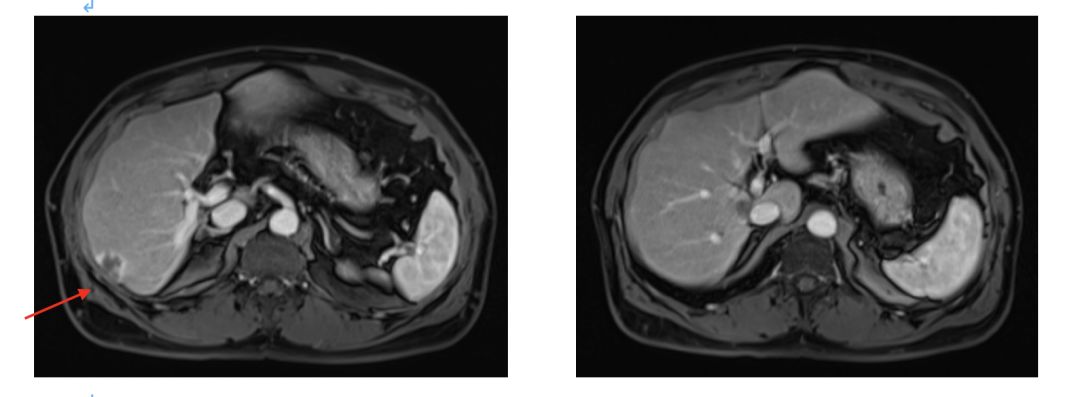

影像学评估 2015.4.7;

4周期评估肿瘤部分缩小;

2015.4.6 CEA下降至435ng/ml;

影像学评估:8周期化疗后,肝脏病灶缩小43%,疗效评价为部分缓解(PR)。